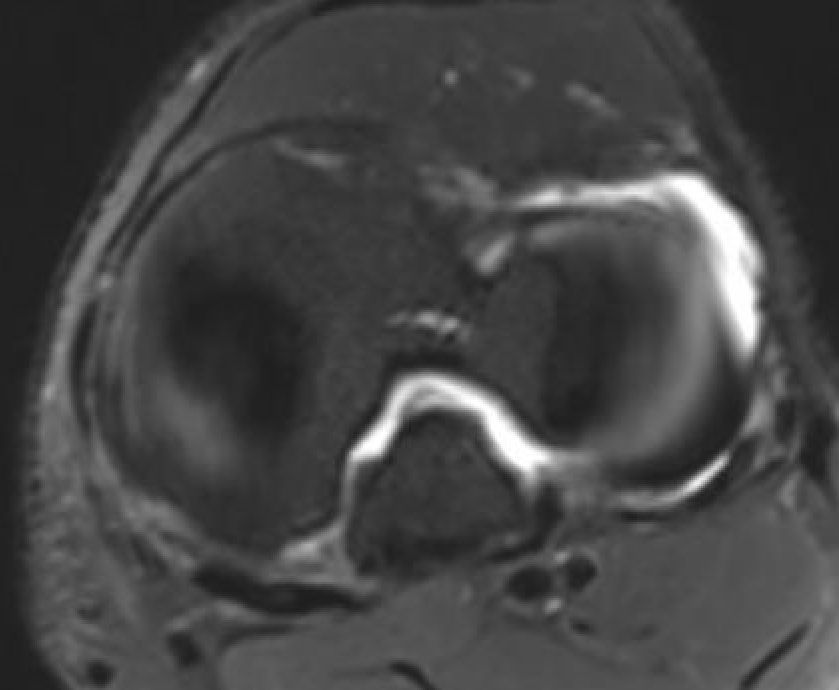

MRI

PCL completely torn